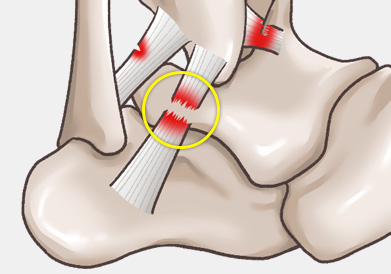

3도 파열의 경우 인대에 대한 봉합술이 필요합니다.

주로 다음 그림처럼 내반(inversion)에 의해 바깥쪽 인대가 파열되는 경우가 흔하며, 그 중에서도 전거비인대 및 종비인대의 손상 여부가 수술을 결정하는 데 가장 중요합니다.

3도 손상의 경우 전거비인대 완전 파열 뿐만 아니라 종비인대의 손상도 흔히 같이 동반되어 있기 때문에

최소 절개를 통해 micro MBO 수술법을 이용하여 단단하게 인대를 봉합하여 재파열의 가능성을 최소로 낮춥니다.